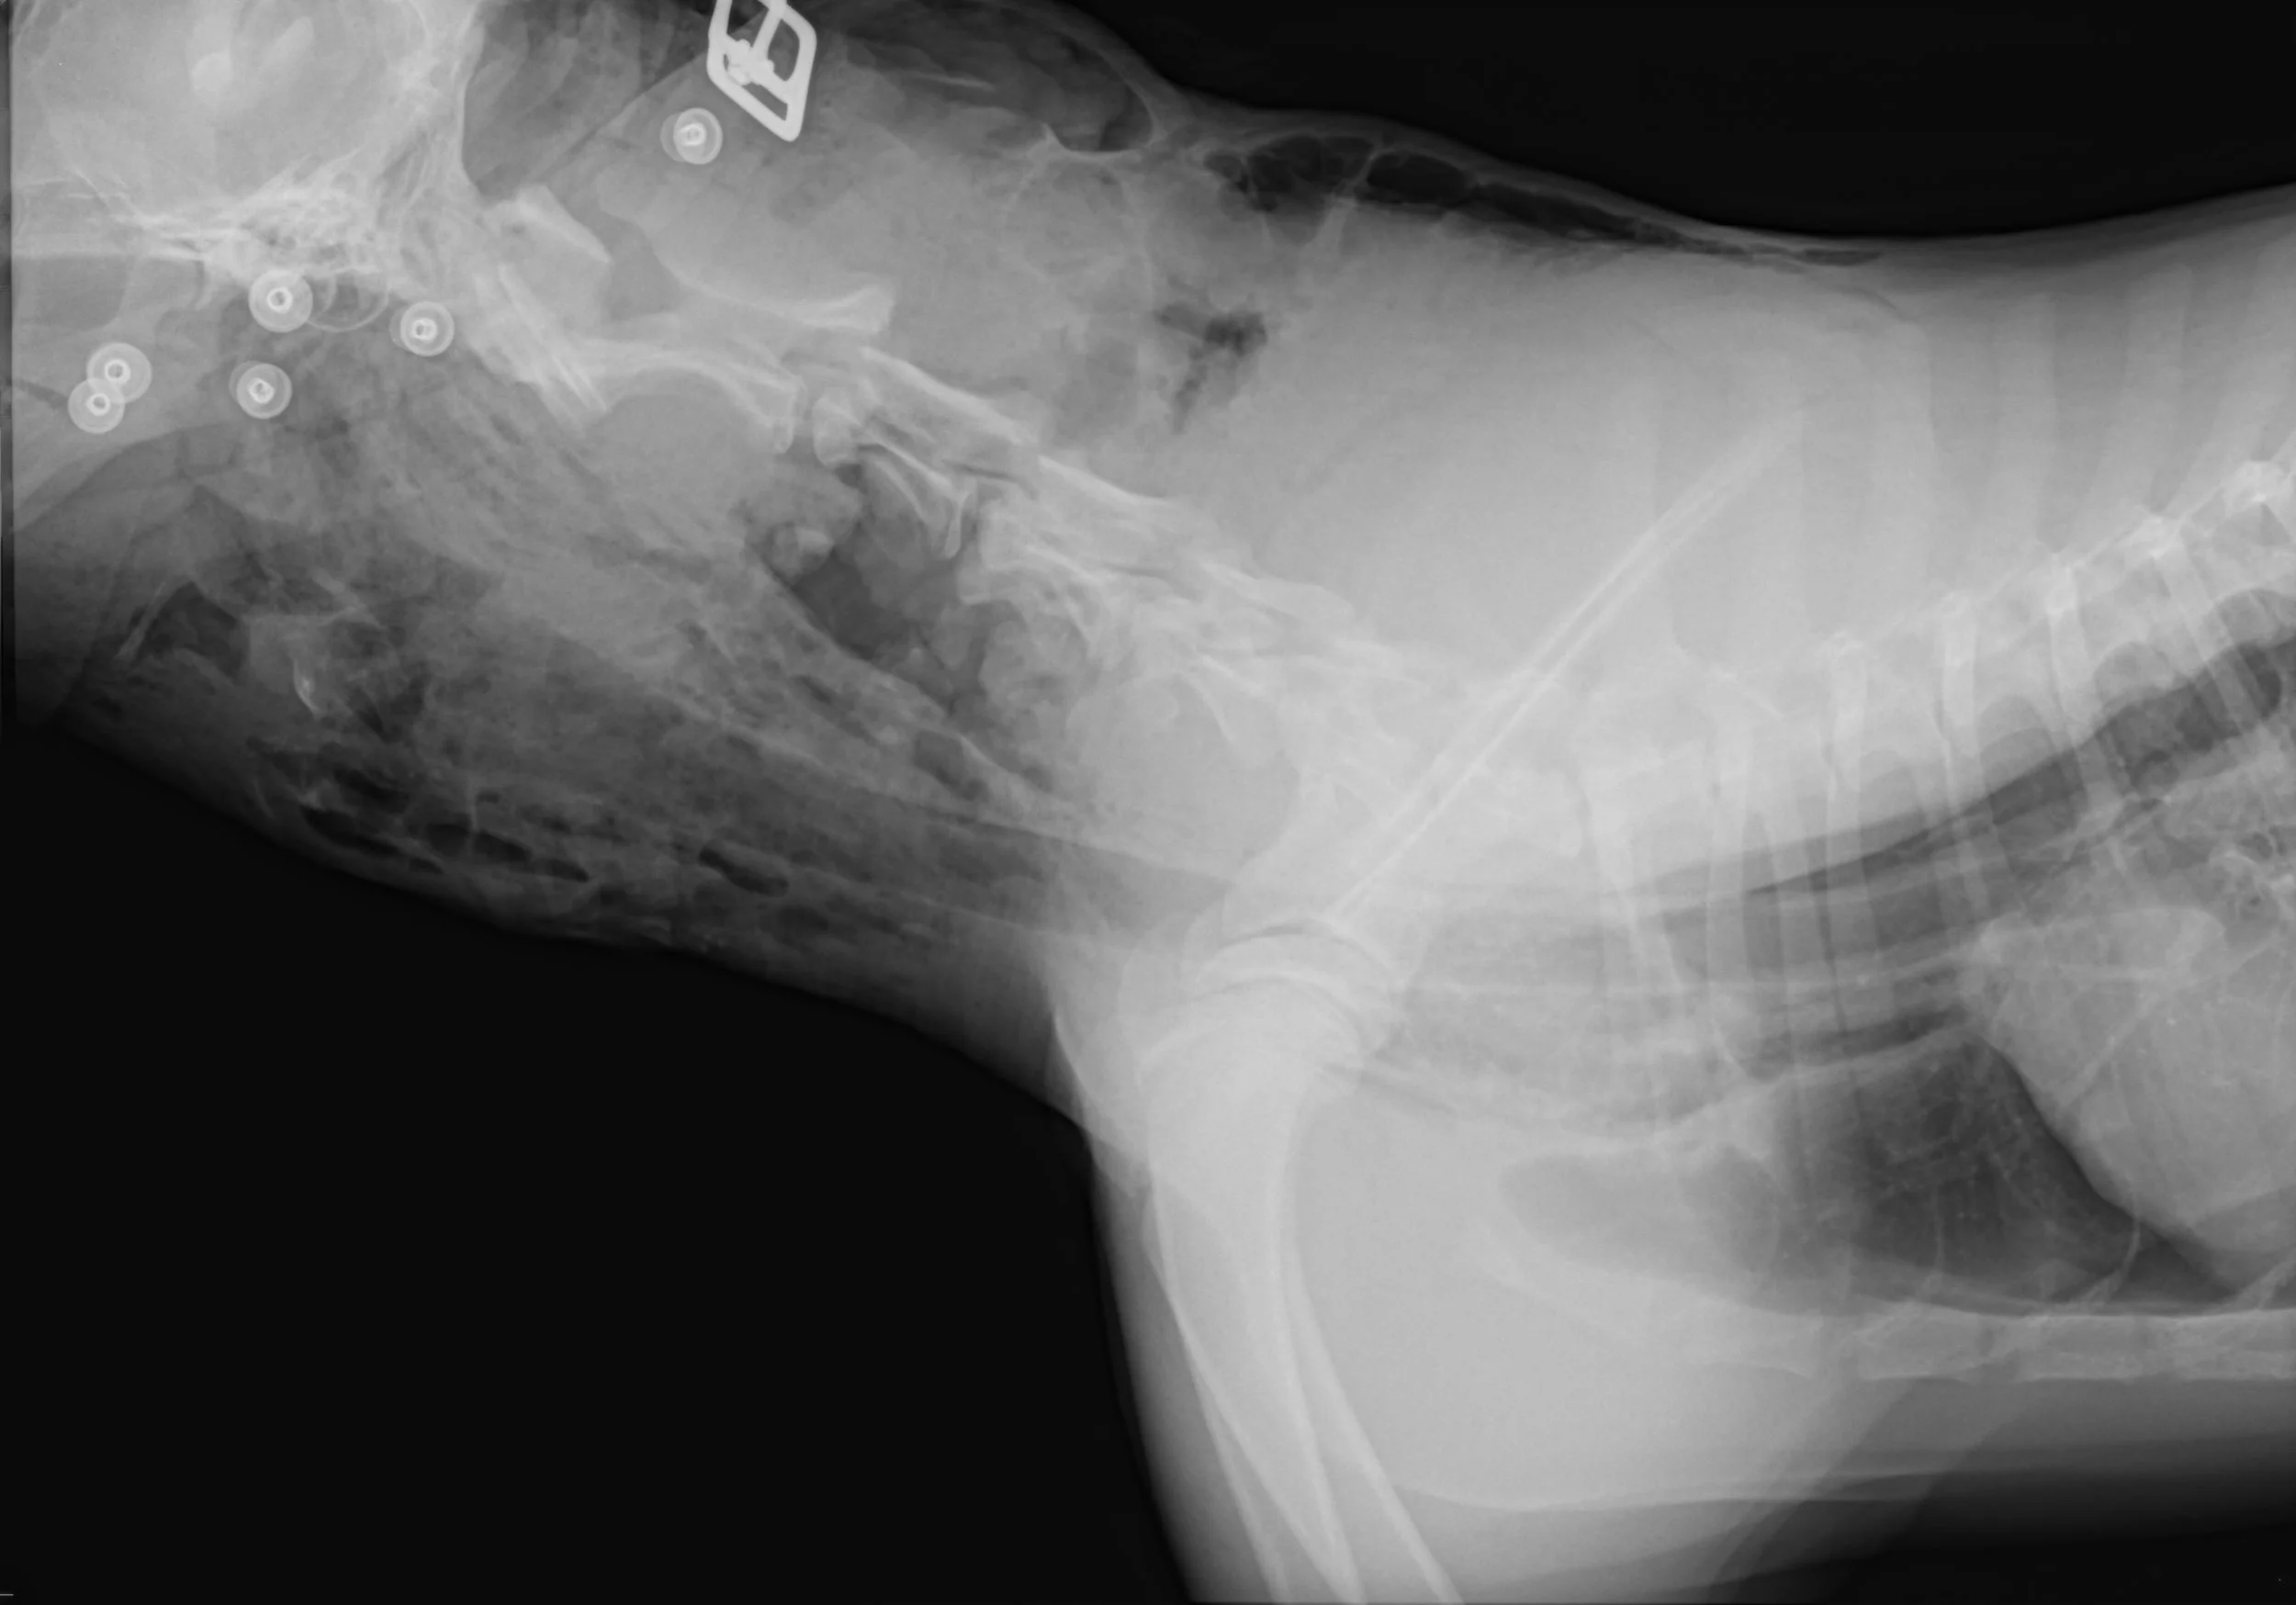

A canine is presented through the emergency and critical care servicer with a history of multiple shearing wounds resulting from injuries sustained from being hit and dragged by a car.

You take survey chest radiograph (above). Is this patient a candidate for adjuvant HBOT? Please discuss the reason(s) for your answer.

ANSWER: The radiograph reveals that this patient has extensive subcutaneous edema and pneumomediastinum. Progression to pneumothorax occurs in some patients with pneumomediastinum. It is not safe to treat a veterinary patient with pneumomediastinum in a monoplace HBOT chamber. If tension pneumothorax should develop while in the chamber, successful intervention might not be possible in a timely fashion. Untreated tension pneumothorax is an absolute contraindication for HBOT (Reference Jain, KK, Textbook of Hyperbaric Medicine Fifth and revised and updated Edition, Hogrefe, 2009, page 76).

The clinician should be aware that pneumothorax can result from causes other than blunt force trauma. For example, in humans it has been reported to result from the use of an air and water cooled turbine burr during a dental procedure (Reference, Shackelford D et al, Diffuse Subcutaneous Emphysema, Pneumomediastinum, and Pneumothorax AFter Dental Extraction. Ann Emerg Med, 1993 Feb; 22[2]: 248-50).